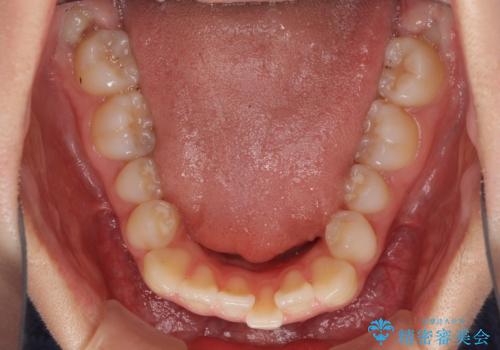

- 前歯のクロスバイトが気になり、インビザラインによる矯正治療を希望して来院された患者様です。

上顎側切歯(上の真ん中から2番目の歯)が舌側転位している場合、インビザラインでは仕上げきれないことが多く、更には無理して動かそうとすると歯髄壊死を起こすリスクが高いと言われています。

インビザラインで歯列を移動する前に、上顎前歯をワイヤー矯正で整え、その後上下歯列をインビザラインにて矯正治療を行うこととしました。

舌側転位している側切歯特有の、切縁の位置が不揃いであったり、根元が内側に引っ込んだ状態であったりという、インビザライン独特の仕上がりになることなく、きれいに整った歯列とすることができました。